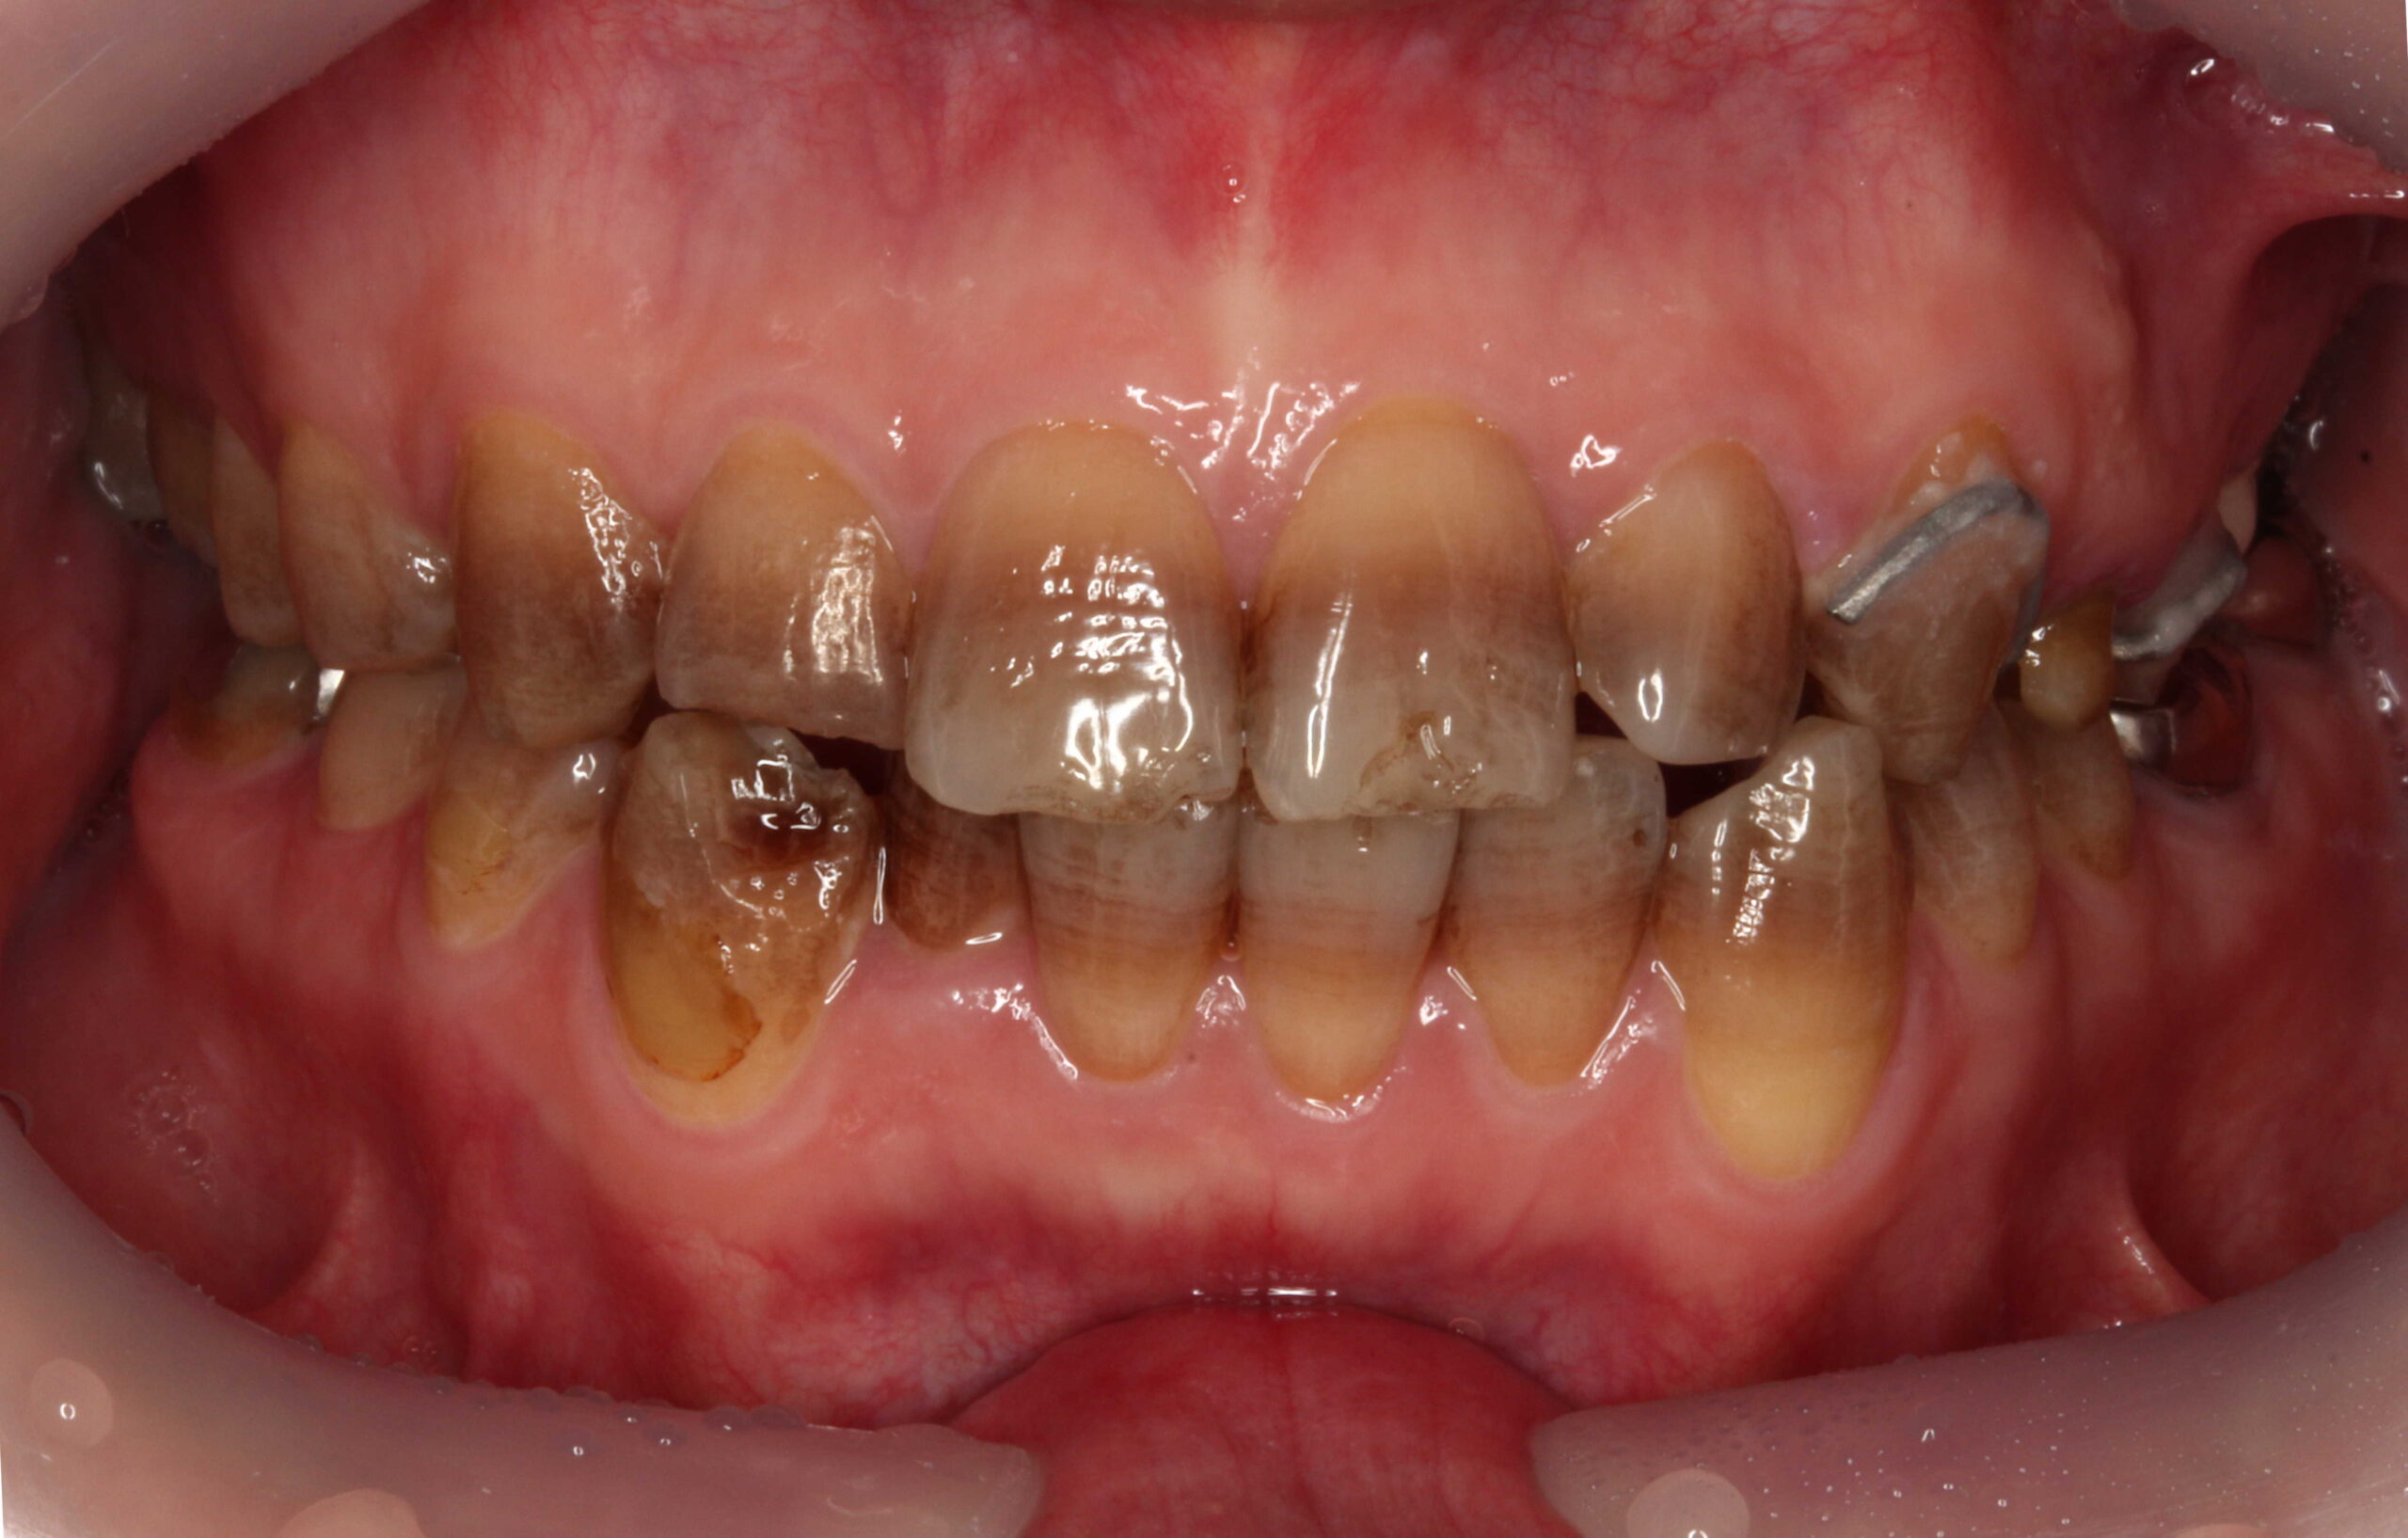

テトラサイクリン歯と失活歯と古いクラウンの症例

こちら、テトラサイクリン歯と失活歯と古いクラウンの症例となっております。

術前 削らないラミネートベニア4本

+クラウン2本

全体的にはホワイトニングを行っています。

テトラサイクリン歯 と 左上2や右下1などの失活歯 にもホワイトニング効果は出ています。

削らないラミネートベニアは極薄のセラミックベニアなので透明感があるので元の歯の色味が透けます。(透過性のないベニアも製作出来ますが、透明感がないので色味が白浮きして不自然になります。)

上の前歯(右上32と左上23) にも、削らないラミネートベニアの前にホワイトニングを行っています。

従来の方法であれば、上前歯6本をラミネートベニアやセラミッククラウンを行うために削って、セラミック材料を被せる方法で行っていました。